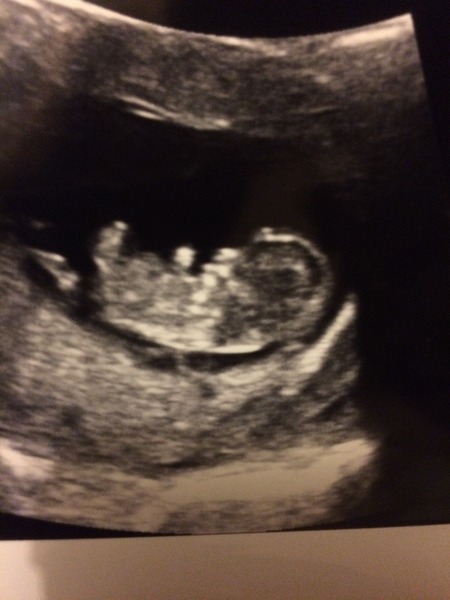

Haven't posted in aages, I had a bit of bleeding recently, then some more yesterday and it was bright red and I panicked so had an early reassurance scan today. All is well, thankfully, and i'm so relieved!! my edd looks to be earlier than i thought, i am measuring 11+2 when by the mw i am 10+3 and my own dates had me at 9+5. So my edd may now be 25/05 but I'll see what happens at the 12 week scan

Glad you got good news kyz. Very cute pic

kyz lovely scan pic! Glad things are ok after your scare.

Great scan kyz